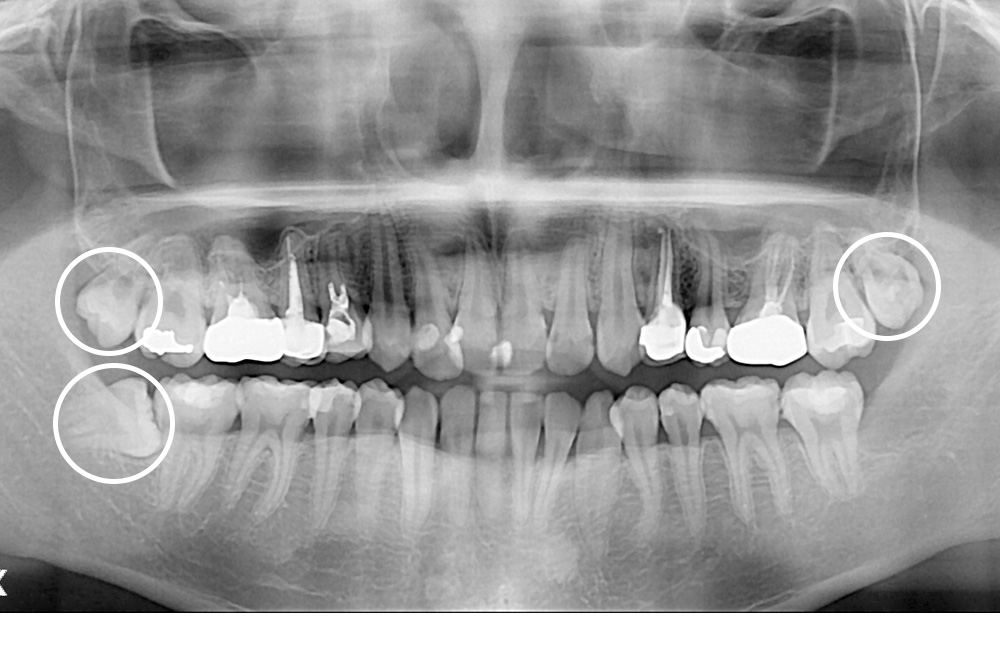

[사랑니] 매복 사랑니 발치

치료전 : 2020-06-03

세종치과는 구강악안면외과학 박사이신 원장님이 발치하는 치과입니다.